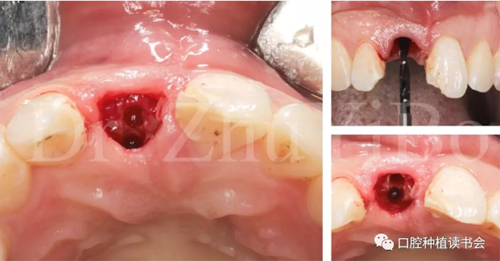

一位年輕女性患者,右上中切牙外傷冠根折2日。

臨床檢查發(fā)現(xiàn):右上中切牙冠根折,斷面位于齦緣下4到5個(gè)毫米。左上中切牙及右上側(cè)切牙,切角缺損,牙髓活力正常(圖7)。

圖7 外傷導(dǎo)致11冠根折

4.2.1微創(chuàng)拔出牙齒,挺出根尖(圖9)

圖9 斷裂牙根需用微創(chuàng)器械拔除

4.2.2 拔牙窩沖洗,定點(diǎn),備洞(圖10)。

圖10 種植窩洞相對(duì)于天然牙長(zhǎng)軸偏向腭側(cè)